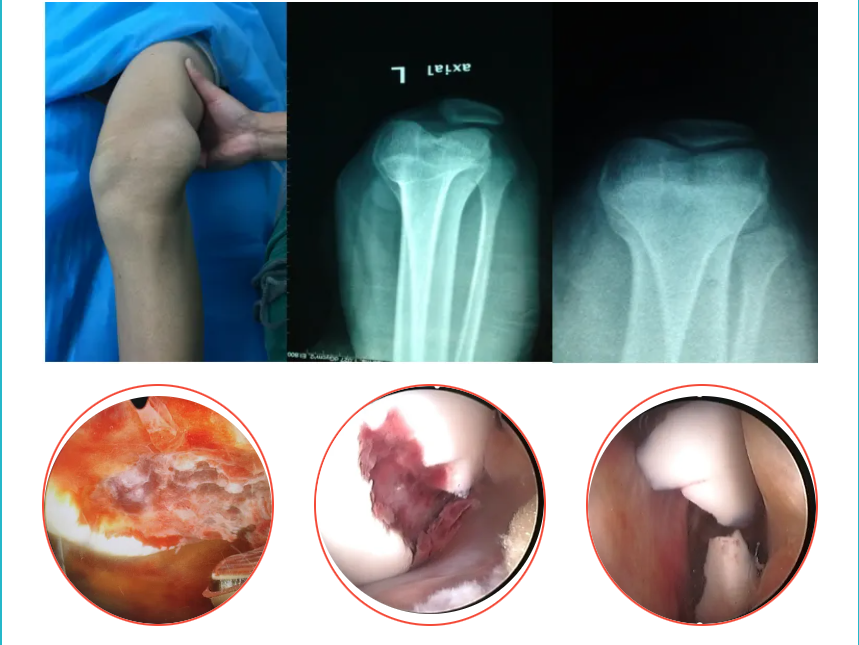

04.髕骨脫位

關(guān)節(jié)鏡下微創(chuàng)行髕股韌帶縫合或者重建